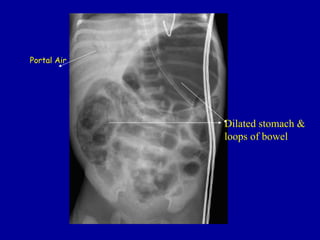

Portal Air

Dilated stomach &

loops of bowel

RADIOLOGICAL FINDINGS

• Portal Venous Gas

– extension of pneumatosis intestinalis into the

portal venous circulation

• linear branching lucencies overlying the liver and

extending to the periphery

• associated with severe disease and high mortality